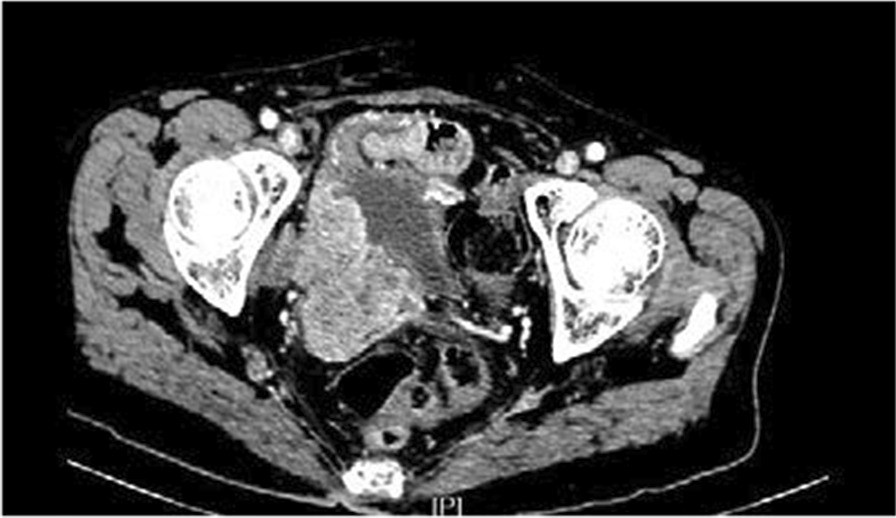

Fig. 5From: Ureteral urothelial carcinoma with squamous cell carcinoma and sarcomatoid carcinoma differentiation: a case reportIrregular soft tissue mass shadows on the right side of the pelvis. Tumour metastasis with invasion of the inferior vena cava and right common iliac artery was consideredBack to article page